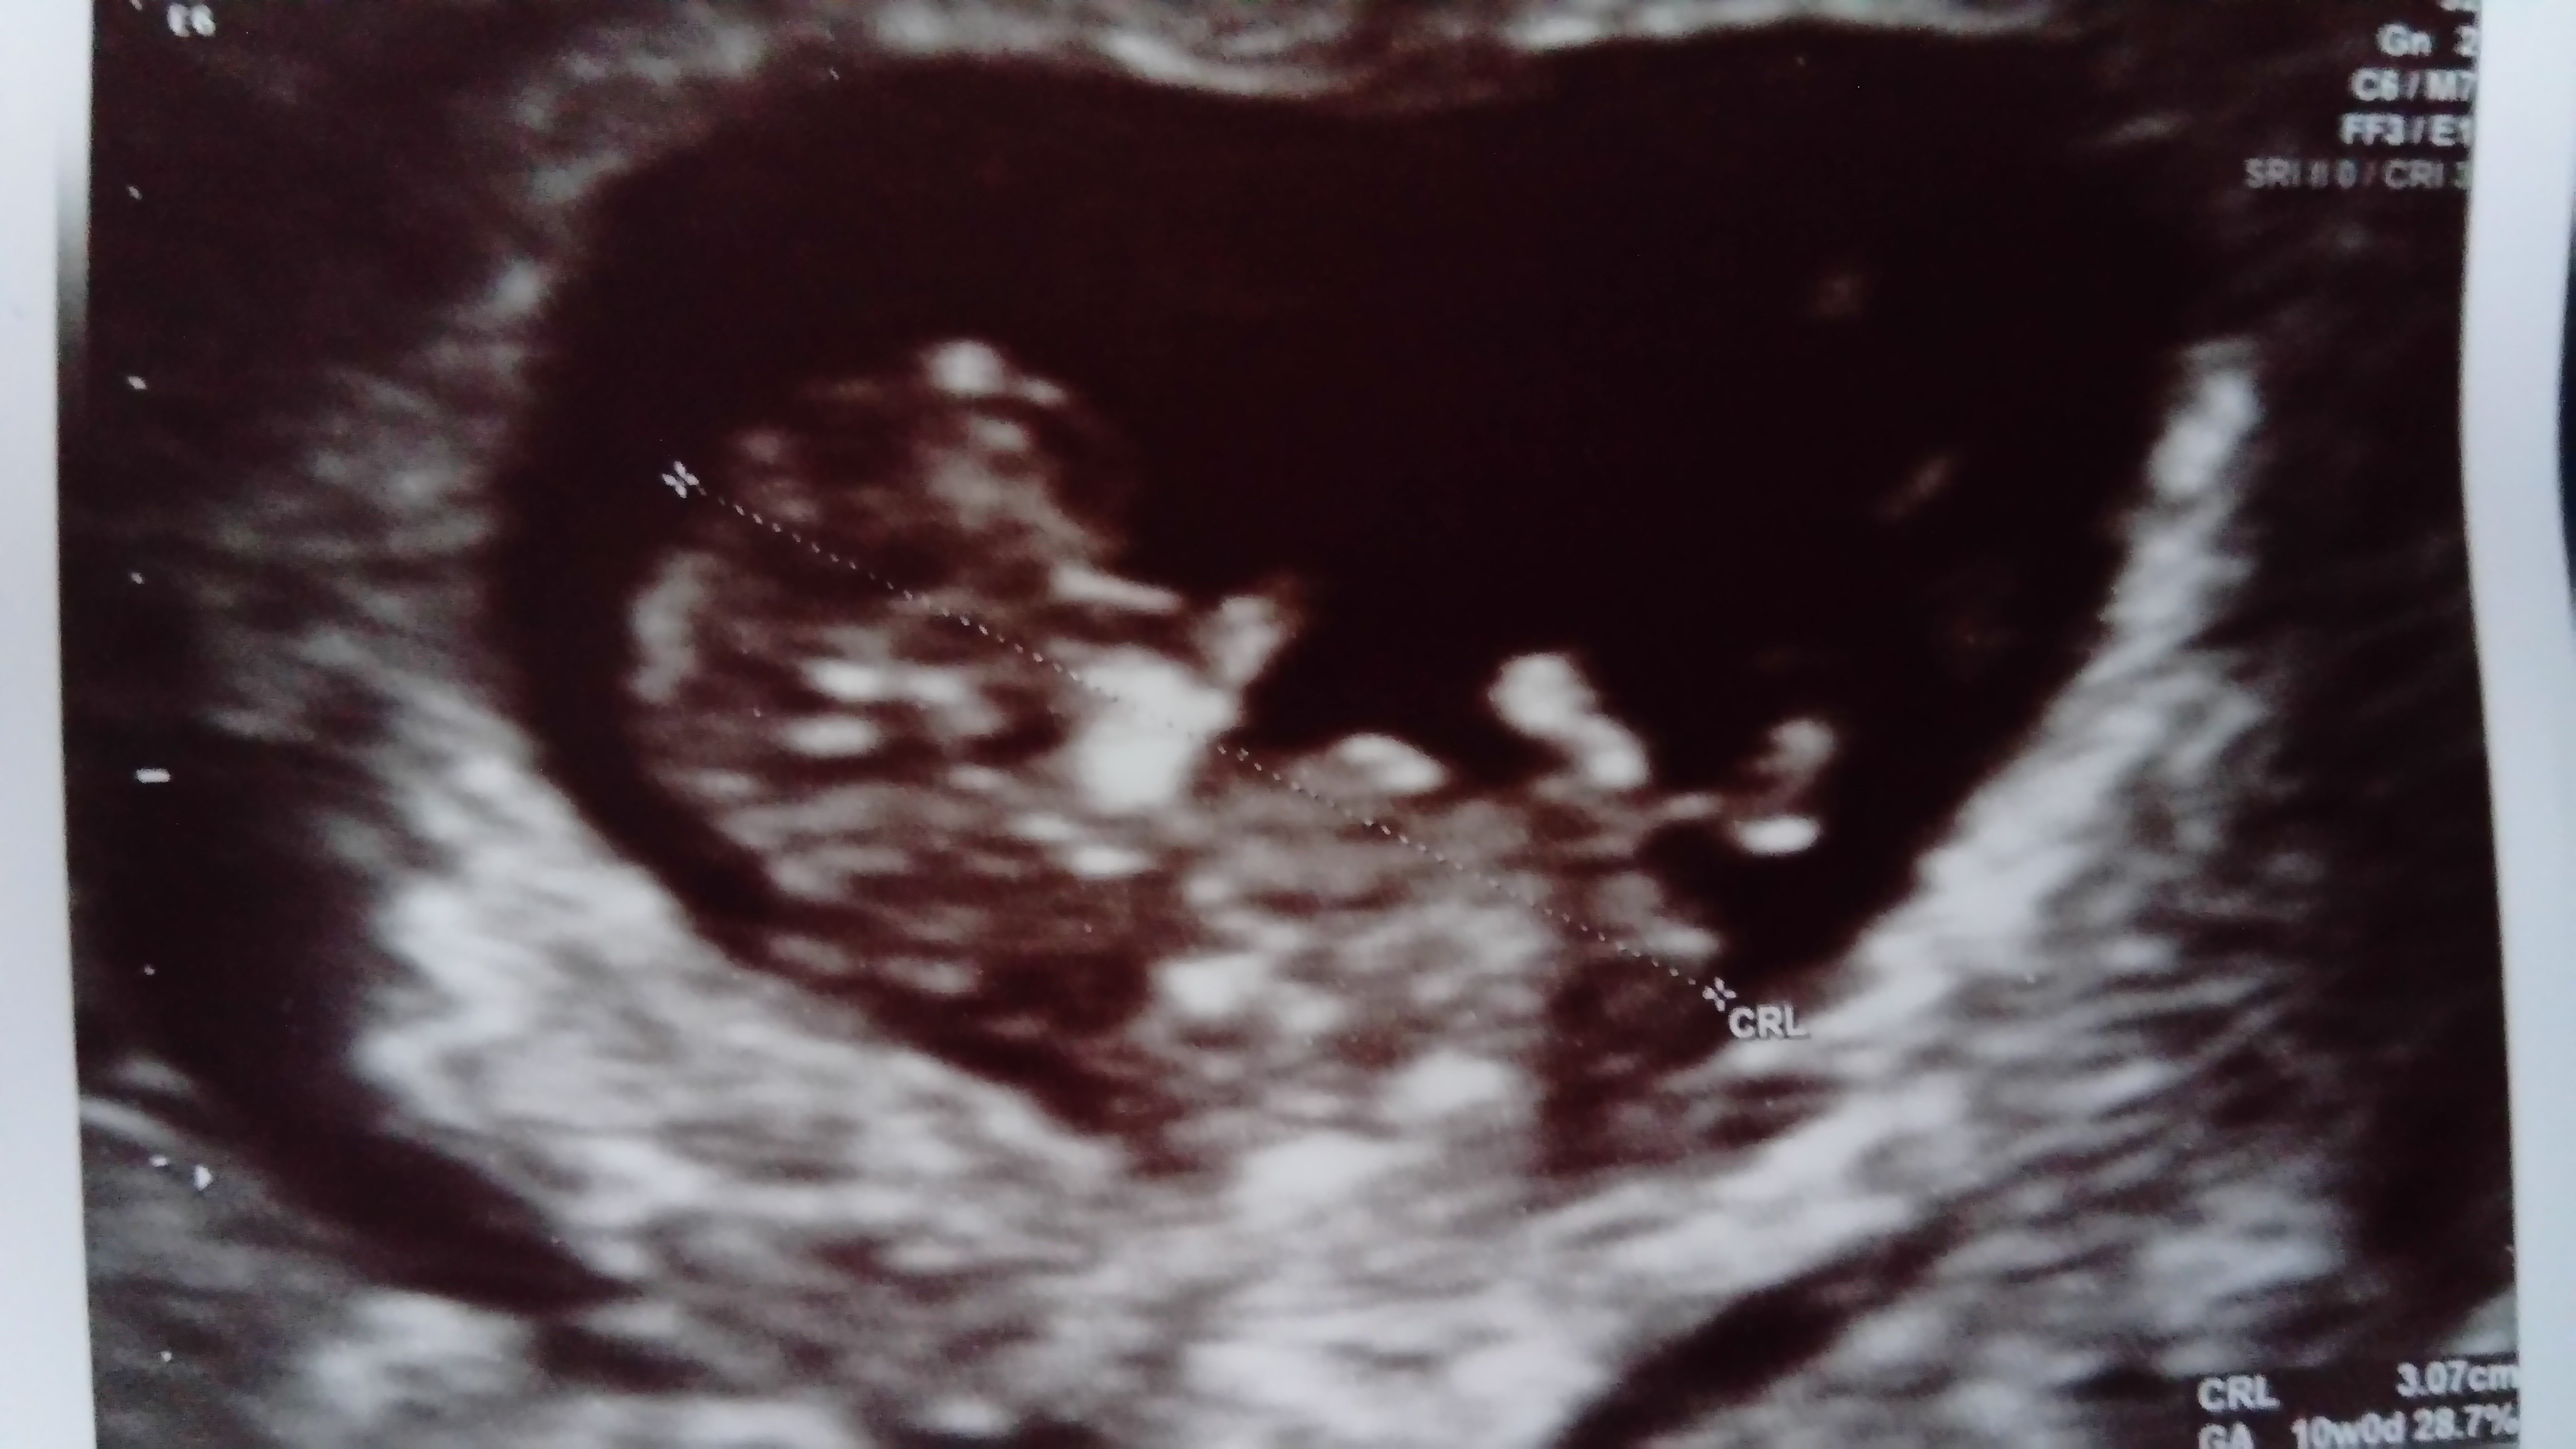

Dziewczyny bardzo miło było mi z Wami przez te niespełna 2 miesiące, no niestety okazało sie na wizycie że serduszko przestało bić [emoji25][emoji25][emoji25] mimo że wiedziałam że wszystko może się zdarzyć, cisza i brak jakiegokolwiek ruchu na USG byly straszne i długo zapadną w pamięć. Dostałam skierowanie do szpitala, jutro muszę się zaopatrzyć w kilka rzeczy do szpitala, bo nawet koszuli nocnej nie mam [emoji52] i w środę mogę przyjechać na zabieg w znieczuleniu ogólnym. Do czwartku będę musiała zostać na oddziale, boję się cholernie tego szpitala. Strasznie przybita jestem, nie sądziłam że tak sie będę czuła. Ehhh teraz będę się pewnie bała próbiwać znowu [emoji25]